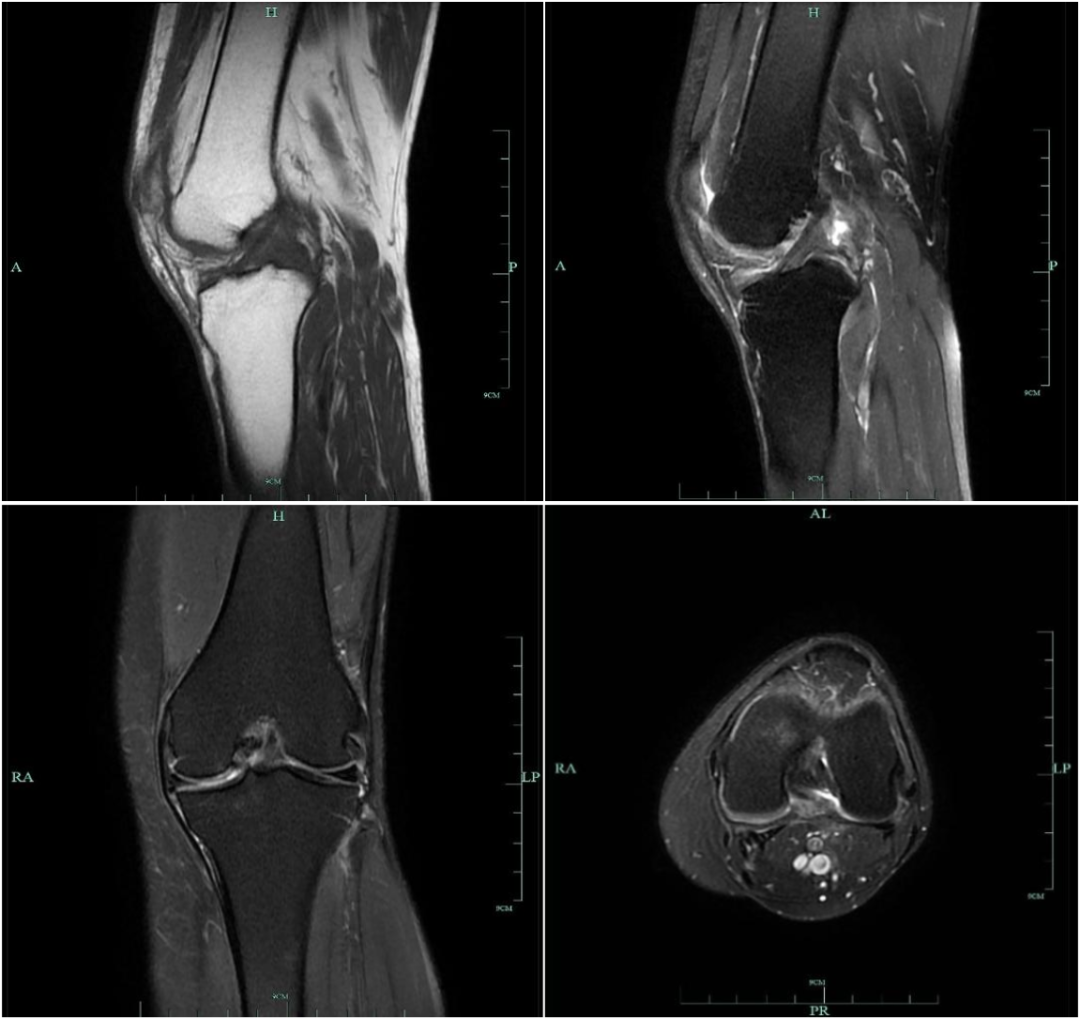

男,30 岁,正常前交叉韧带,T1 及 T2 加权序列矢状面

女,20 岁,正常前交叉韧带,扇形,韧带前为低信号,后为中等信号纤维束

男 40 岁,正常前交叉韧带,扇形,前为低信号,后为中等信号纤维束